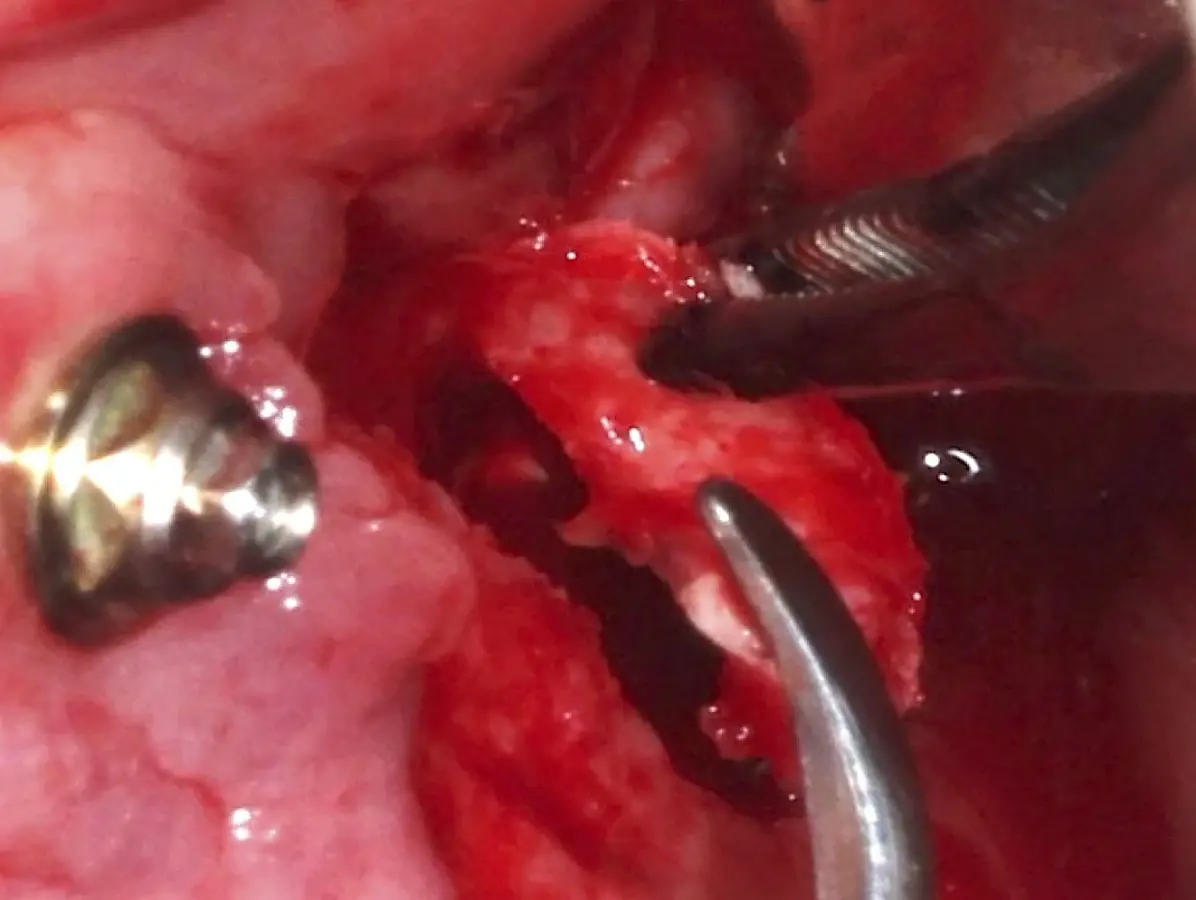

Figura 16. Delimitación y osteotomía por desgaste de la ventana lateral con el inserto plano de punta diamantada (a). Retiro del bloque óseo (b).

Figura 23. Delimitación y osteotomía por desgaste de la ventana lateral con el inserto redondo de punta diamantada.

Figura 24. Fractura del bloque óseo con la ayuda de un martillo e instrumento romo.